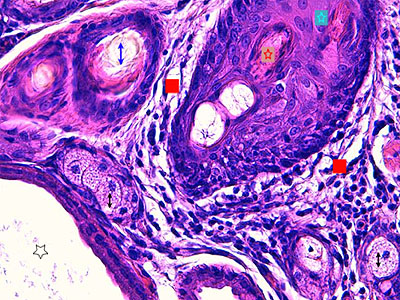

Photo 4 : (Hémalun Eosine X 200) : Hyperplasie des infundibula et isthmes folliculaires,

des canaux et des glandes sébacés; inflammation mononucléée du pourtour isthmique

des follicules pileux et des glandes sébacées; le cycle folliculaire est normal.

Légendes de la Photo 4 :

- Pointe de flèche rouge = tige pilaire dans isthme folliculaire

- Étoile rouge = fundus de glande sudorale épitrichiale

- Étoile turquoise = lobules de glande sébacée hyperplasique

- Flèche double noire = canal sébacé hyperplasique et hyperkératosique (orthokératose)

- Carré rouge = follicule pileux en phase anagène

- Étoile rouge = infiltrat inflammatoire lympho-plasmocytaire péri-isthmique